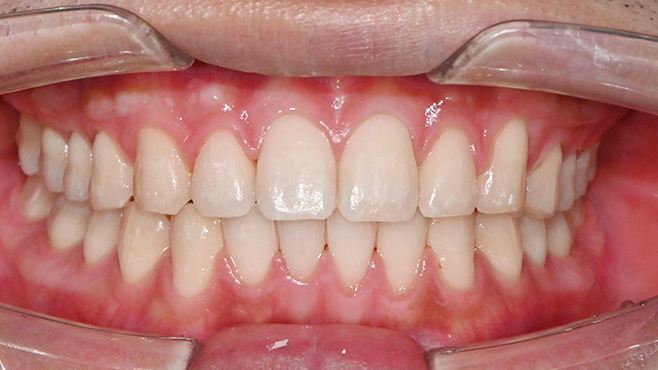

치과가 무서워 10년 동안 미뤄온 임플란트 수술 그 결과는?

2026.01.21